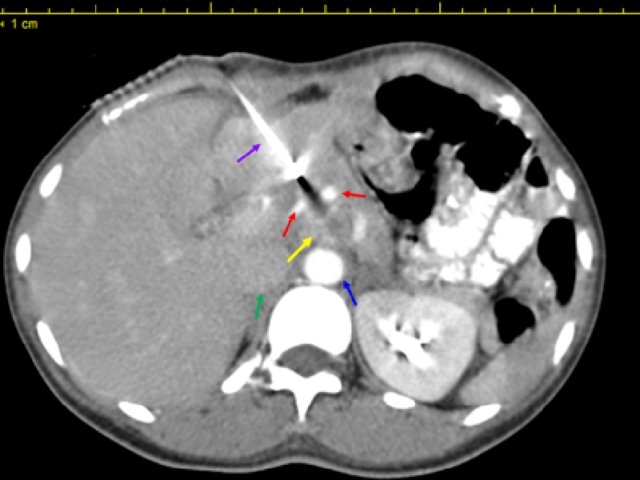

治疗中影像学显示

(黄色箭头为转移淋巴结,红色箭头为肿瘤前方小动脉,绿色箭头为下腔静脉,蓝色箭头为腹主动脉,紫色箭头为插植针)